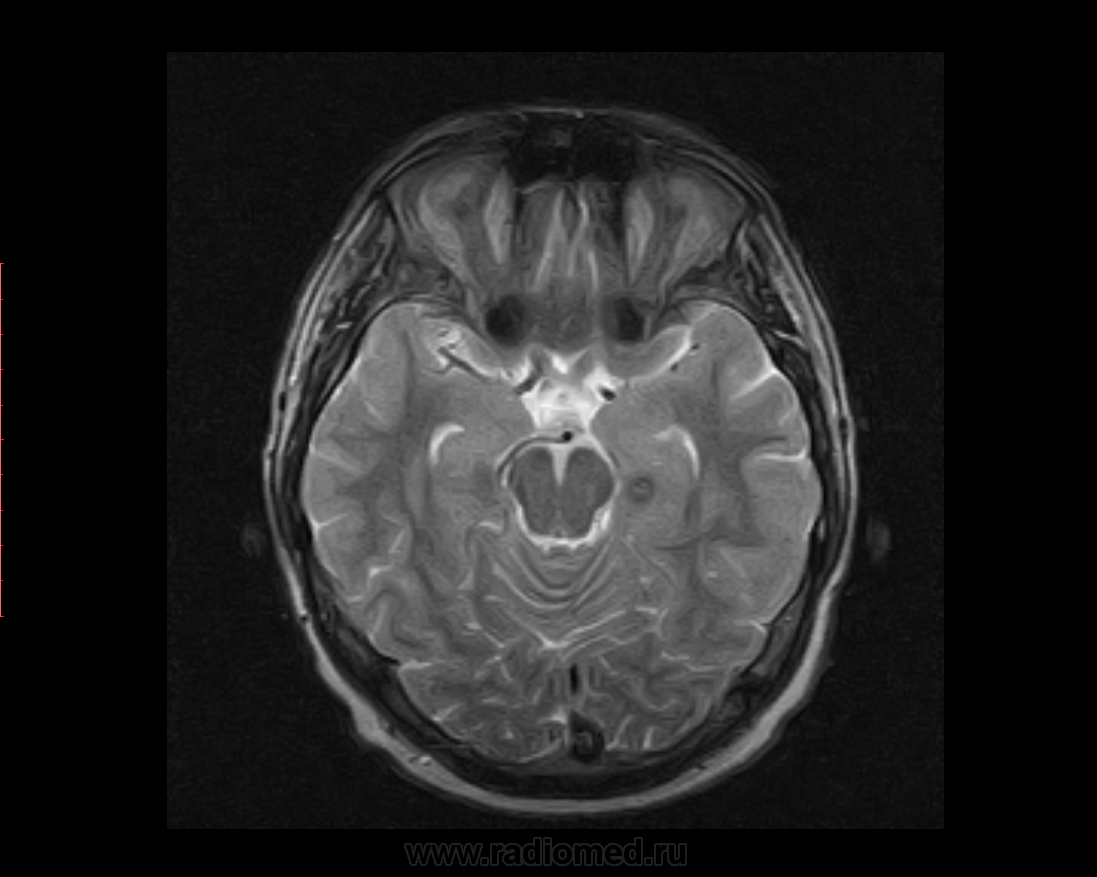

М, 27 лет. Жалобы на головные боли. ЧМТ в анамнезе. Стационар выставил внутримозговую гематому по КТ, полечили, отпустили.  К нам пришел на контроль.

Локализация таламус, граница коркового/мозгового, похоже на множественные кавернозные ангиомы. То, что в левой лобной?

Хочу посоветоваться с коллегами).  Дифференциальный ряд построить. Например токсоплазмоз, метастазы....в общем жду.

Сложно представить у молодого человека и каверномы, и метастазы одновременно.

Наверное, все же множественные каверномы, слева -осложненная кровоизлиянием.

Пришел к выводу, что сдесь все таки не каврномы, а мелкоочаговые кровоизлияния (ДАП). Учитывая травму и пребывание после этого  пациента в коме.